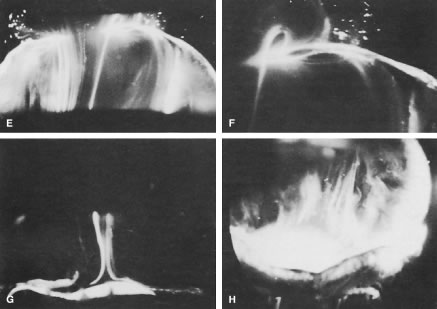

The sclera, choroid, and retina can be dissected and the naked vitreous body can be maintained intact and attached to the anterior segment of the eye (Fig. 2A). This enables study of internal vitreous morphology without a loss of intraocular orientation. However, depending on the person's age and consequently the degree of vitreous liquefaction,55 the dissected vitreous will remain solid and intact in young persons or will be flaccid and collapse in older individuals. Consequently, vitreous turgescence must be maintained to avoid distortion of intravitreal structure. Immersion of a dissected vitreous specimen that is still attached to the anterior segment into a physiologic solution maintains vitreous turgescence and avoids structural distortion (see Fig. 2B). The limitations induced by the transparency of the vitreous were overcome by Goedbloed,98 Friedenwald and Stiehler,99 and Eisner87 who employed darkfield slit illumination of the vitreous body to achieve visualization of intravitreal morphology. Illumination with a slit-lamp beam directed into the vitreous body from the side and visualization of the illuminated portion from above produces an optical horizontal section of the vitreous body.100 The illumination/observation angle of 90 degrees that is achieved by using this technique maximizes the Tyndall effect and, thus, overcomes the limitations induced by vitreous transparency. Furthermore, the avoidance of any tissue fixation eliminates the introduction of many of the artifacts that flawed earlier investigations. Recent studies have used these techniques to investigate human vitreous structure. Within the adult human vitreous there are fine, parallel fibers coursing in an anteroposterior direction18,100–102 (Figs. 3B and C and 4). The fibers arise from the vitreous base (see Figs. 3H and 4) where they insert anterior and posterior to the ora serrata (see Fig. 3H). As the peripheral fibers course posteriorly they are circumferential with the vitreous cortex, whereas central fibers undulate in a configuration parallel with Cloquet's canal.85 The fibers are continuous and do not branch. Posteriorly, these fibers insert into the vitreous cortex (see Fig. 3E and F).

Fig. 2. Human vitreous dissection. A. Vitreous from a 9-month-old child. The sclera, choroid, and retina were dissected off the vitreous body, which remains attached to the anterior segment. A band of gray tissue can be seen posterior to the ora serrata. This is neural retina that was firmly adherent to the vitreous base and could not be dissected. The vitreous body is solid and although situated on a surgical towel exposed to room air maintains its shape; because of the young age of the donor, the vitreous is almost entirely gel. B. Human vitreous dissected of the sclera, choroid, and retina and attached to the anterior segment. The specimen is mounted on a Lucite frame using sutures through the limbus and then immersed in a Lucite chamber containing an isotonic, physiologic solution. This maintains the turgescence of the vitreous and avoids collapse and artifactual distortion of the vitreous structure. (A Courtesy of the New England Eye Bank, Boston, MA. B from Sebag J, Balazs EA: Pathogenesis of C.M.E: Anatomic consideration of vitreo-retinal adhesions. Surv Ophthalmol 28[Suppl]:493, 1984.)

Fig. 3. Human vitreous morphology. Human vitreous structure visualized by dark-field slit illumination. All photographs are oriented with the anterior segment below and the posterior pole above. A. Posterior vitreous in the left eye of a 52-year-old man. The vitreous body is enclosed by the vitreous cortex. There is a hole in the prepapillary (small, to the left) vitreous cortex. Vitreous fibers are oriented toward the premacular region. B. Posterior vitreous in a 57-year-old man. A large bundle of prominent fibers is seen coursing anteroposteriorly and entering the retrocortical space by way of the premacular vitreous cortex. C. Same photograph as B, at higher magnification. D. Posterior vitreous in the right eye of a 53-year-old woman. There is posterior extrusion of vitreous out the prepapillary hole (to the right) and premacular (large extrusion to the left) vitreous cortex. Fibers course anteroposteriorly out into the retrocortical space. E. Horizontal optical section of the same specimen as D, at a different level. A large fiber courses posteriorly from the central vitreous and inserts into the premacular vitreous cortex. F. Same view as E, at higher magnification. The large fiber has a curvilinear appearance because of traction by the vitreous extruding into the retrocortical space (see D). However, because of its attachment to the posterior vitreous cortex, the fiber arcs back to its point of insertion. G. Anterior and central vitreous in a 33-year-old woman. Cloquet's canal is seen forming the retrolental space of Berger. H. Anterior and peripheral vitreous in a 57-year-old man. The specimen is tilted forward to enable visualization of the posterior aspect of the lens and the peripheral anterior vitreous. To the right of the lens there are fibers coursing anteroposteriorly that insert into the vitreous base. These fibers “splay out” to insert anterior and posterior to the ora serrata. (A, E, and F from Sebag J, Balazs EA: Pathogenesis of C.M.E.: Anatomic consideration of vitreo-retinal adhesions. Surv Ophthalmol 28[Suppl]:493, 1984. B, C from Sebag J, Balazs EA: Morphology and ultrastructure of human vitreous fibers. Invest Ophthalmol Vis Sci 30:187, 1989. D, G, and H from Sebag J: The Vitreous: Structure, Function and Pathobiology. New York, Springer-Verlag, 1989. Specimens were courtesy of the New York Bank for Sight and Restoration, New York, NY.)

Fig. 4. A. Vitreous base morphology. Vitreous structure in a 58-year-old woman. Fibers course anteroposteriorly in the central and peripheral vitreous. Posteriorly, fibers orient to the premacular region. Anteriorly, the fibers “splay out” to insert into the vitreous base. B. Fibers of the peripheral anterior vitreous forming the anterior loop. This configuration can provide the scaffold for cell migration and proliferation in the pathophysiology of anterior proliferative vitreoretinopathy. (A from Sebag J, Balazs EA: Pathogenesis of C.M.E.: Anatomic consideration of vitreo-retinal adhesions. Surv Ophthalmol 28[Suppl]:493, 1984. B from Sebag J: The Vitreous: Structure, Function and Pathobiology. New York, Springer-Verlag, 1989. Specimen in A courtesy of the New England Eye Bank, Boston, MA.)